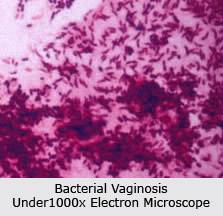

รูปที่ 5 เชื้อแบคทีเรียนานาพันธ์ที่อยู่ในช่องคลอดราวกับสวนสัตว์นี้ ทำให้เกิดภาวะช่องคลอดติดเชื้อได้